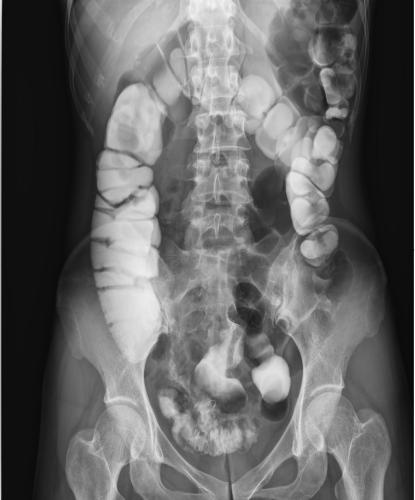

其次,數(shù)字化成像極大地提高了圖像的清晰度、對比度、分辨率,與傳統(tǒng)的胃腸機(jī)相比,空間分辨率可提高一到兩倍,圖像質(zhì)量明顯提升。還具有視頻保存回放功能,檢查結(jié)束后,仍可通過視頻回放對病人進(jìn)行診斷,不需要重復(fù)檢查。由于胃腸道疾病的癥狀大同小異,缺乏特征性,特別是一些早期無癥狀的疾病如早期胃癌或較小的病變在其中受益匪淺。動態(tài)DRF胃腸道造影高清圖像

動態(tài)DRF胃腸道造影高清圖像